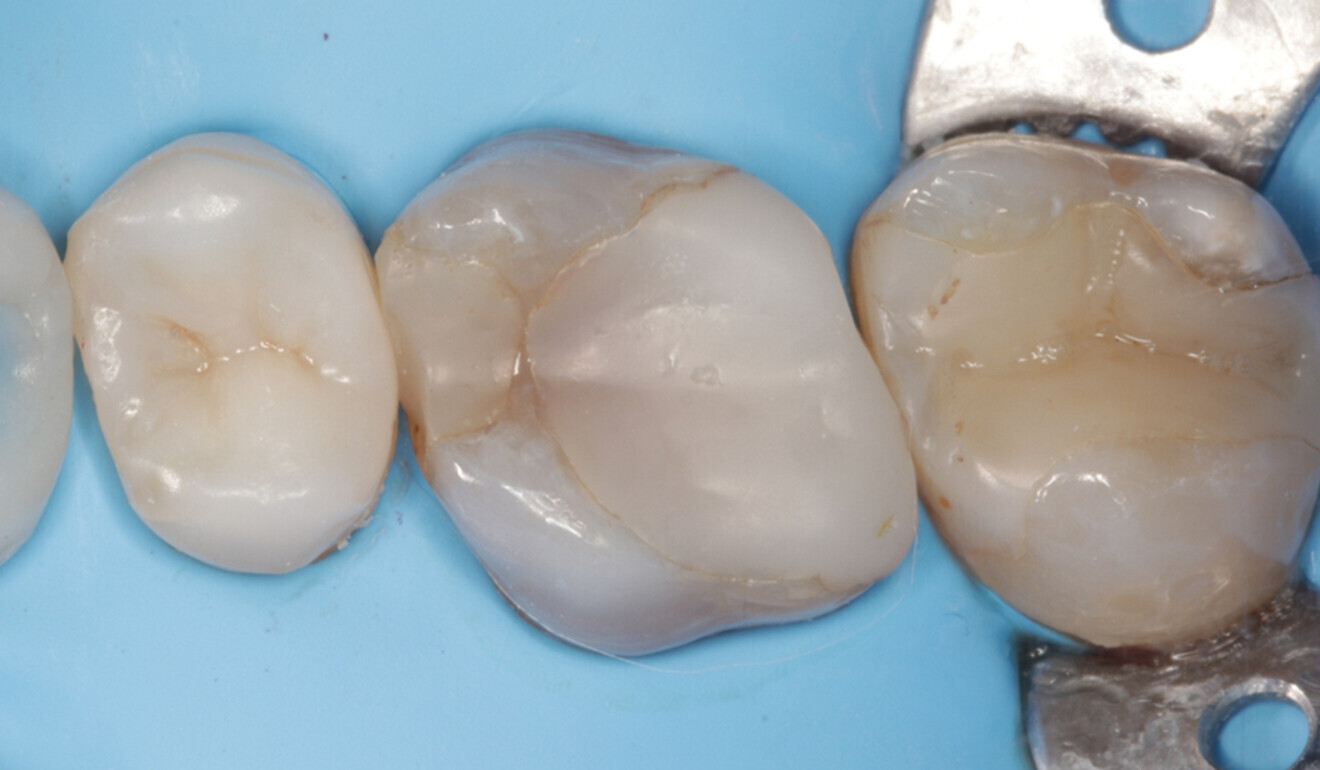

Fig. 17: Occlusal surface after surface modelling with CLEARFIL MAJESTY ES-2 Universal and initial polishing, palatal view. (Image: Kuraray Noritake Dental)